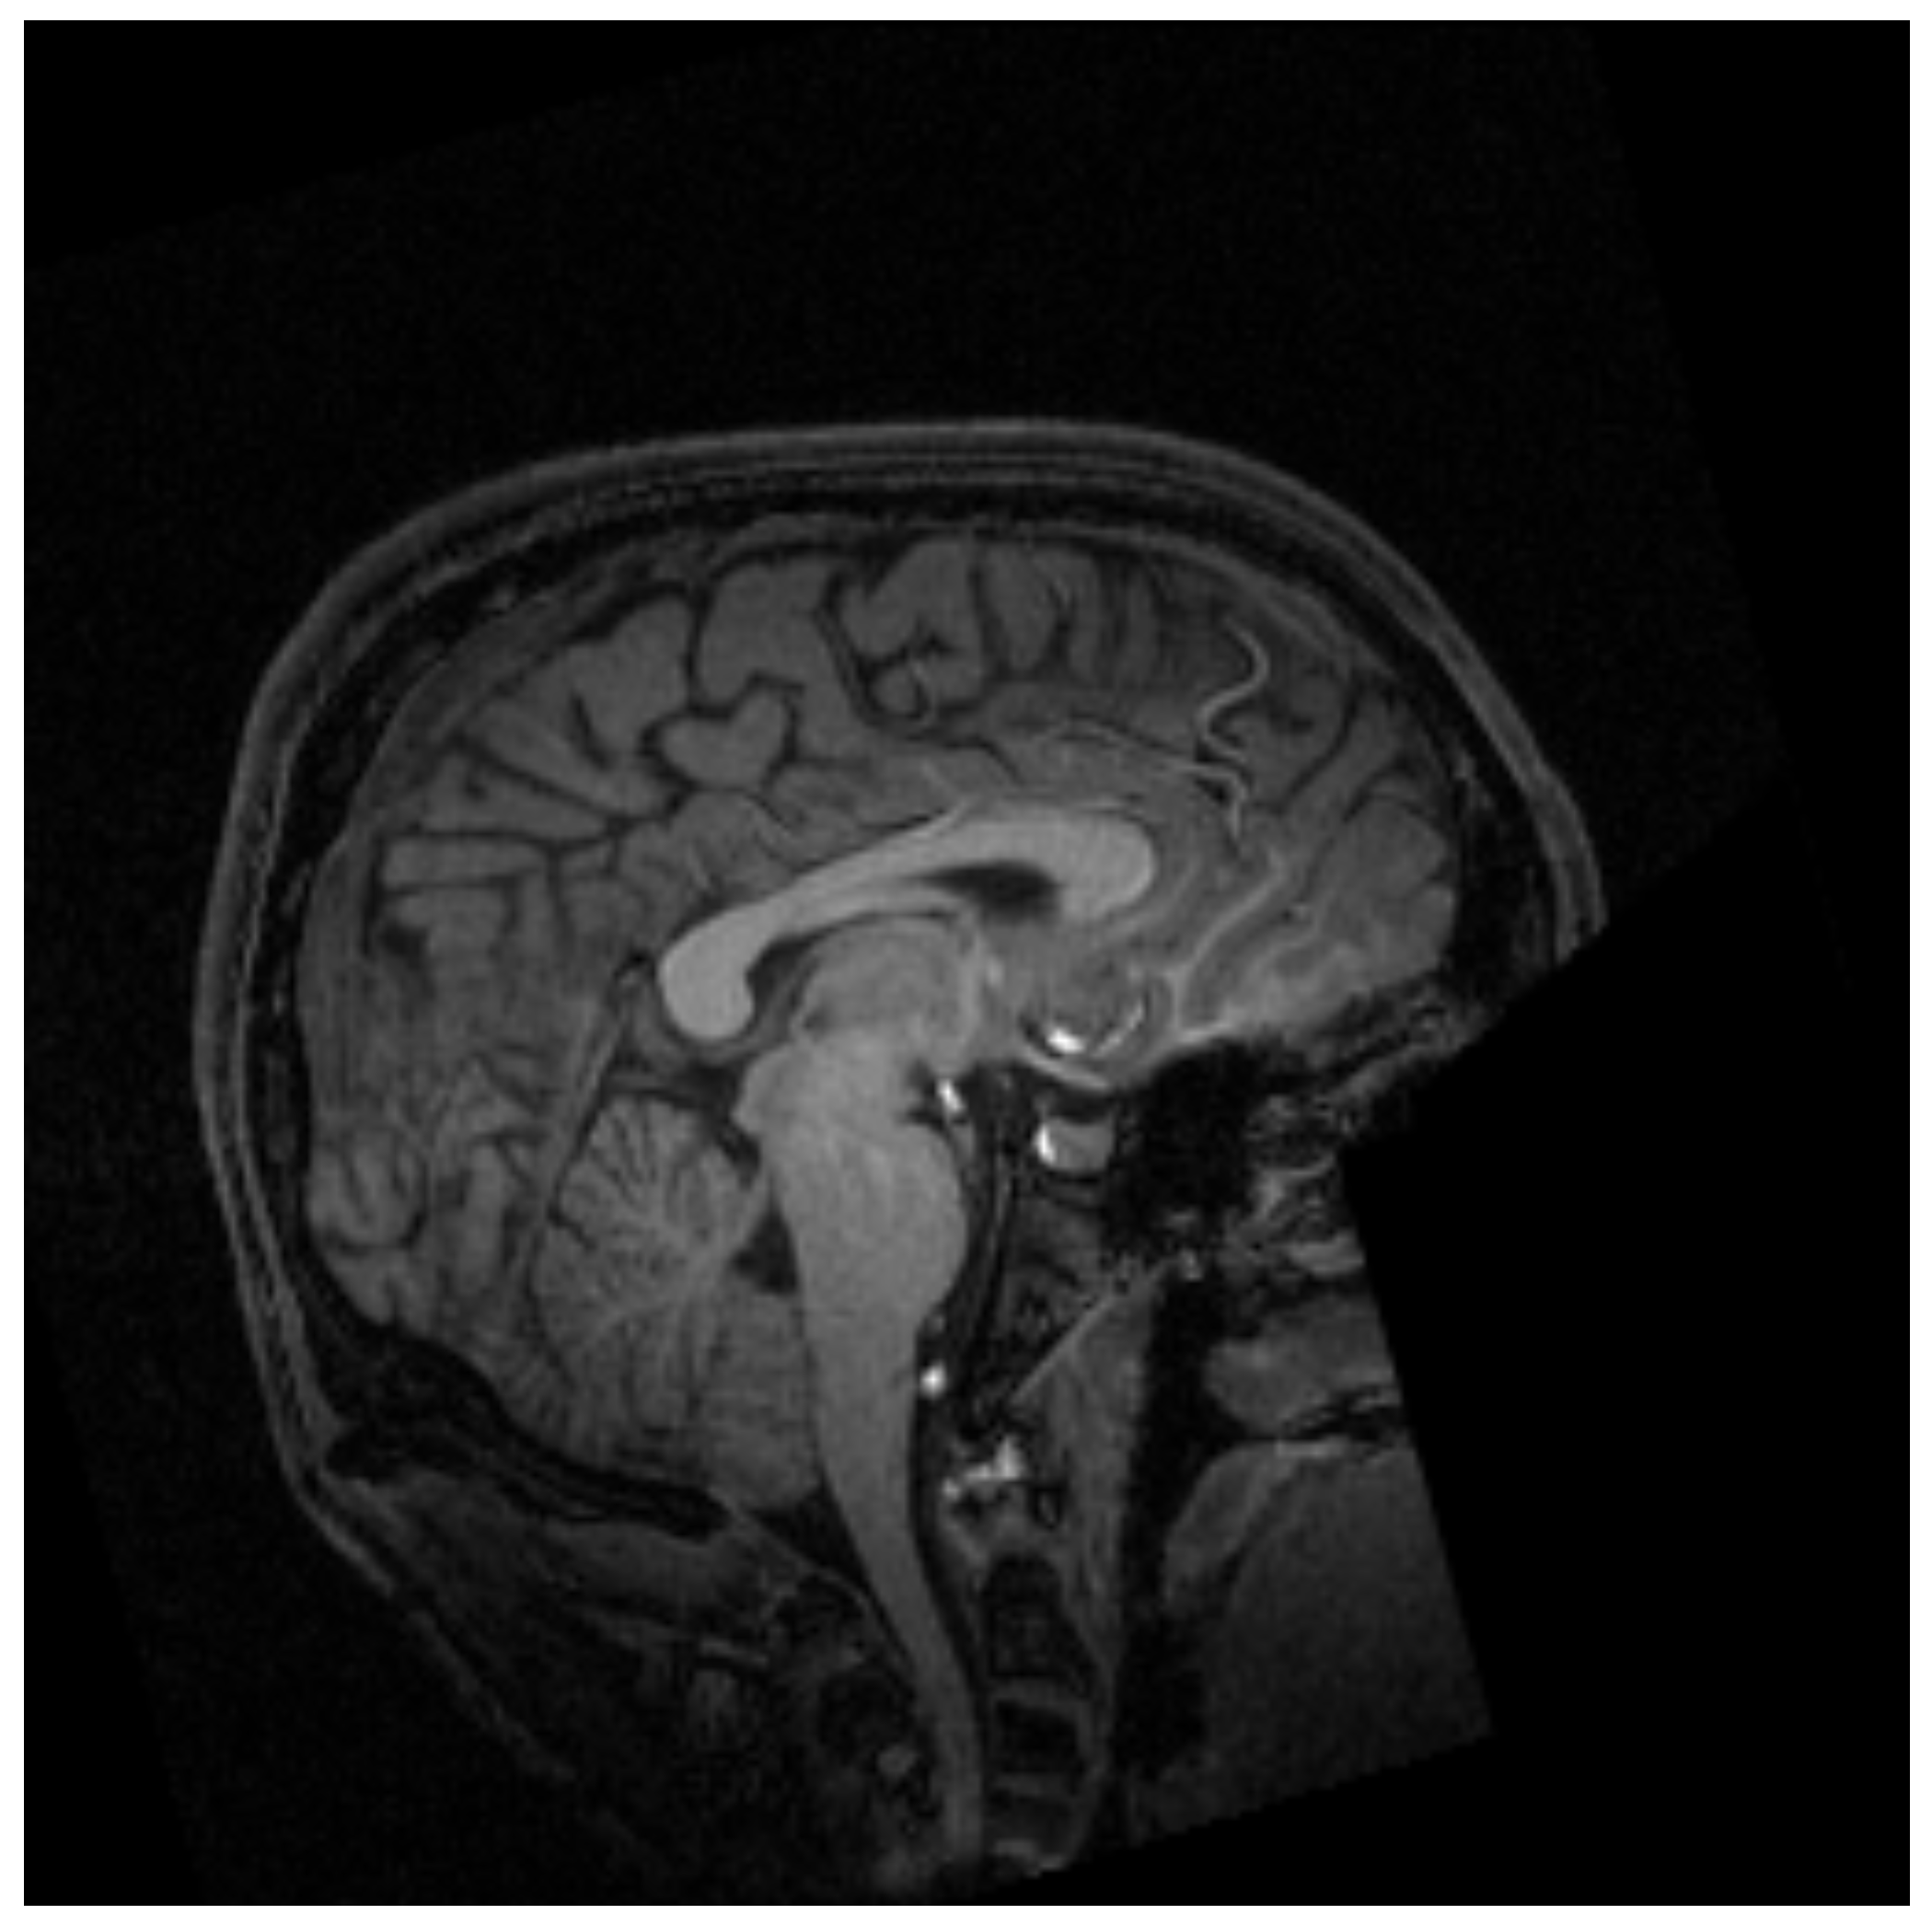

MRI is a non-invasive technique widely used in medicine to obtain the necessary medical images for further diagnosis. This technique is based on the physical phenomenon of resonance. It consists of the transition between different energy states when an atomic nucleus is introduced into an external magnetic field of a characteristic frequency. This frequency, known as the Larmor frequency, corresponds to the precession frequency of the protons inside the nucleus. When a magnetic field is applied, the protons absorb the energy and raise it to a higher level. Once the magnetic field is removed, the protons decay to the ground state. MRI measures the time and energy released from this last transition. Due to its environment, those two values will be different for each proton. Then, applying the inverse Fourier transform to the obtained data, the image is created with different contrast for each component of the body [14] as shown in Figure 1.

Figure 1. Example of magnetic resonance imaging of the cranial region [15].